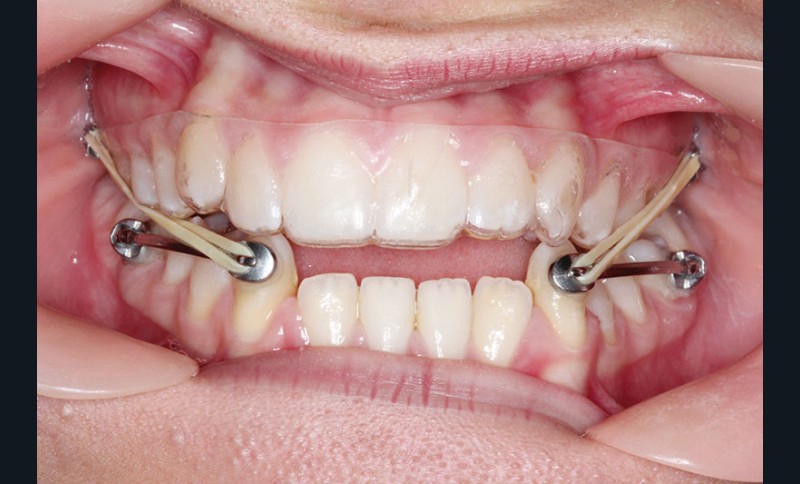

1re phase : recul des secteurs latéraux mandibulaires avec le Motion Classe III Carriere (fig. 4 à 6)

Nous mettons en place des bras latéraux Motion associés à des élastiques intermaxillaires ancrés sur des brackets sur 17 et 27 et une gouttière thermoformée maxillaire portée jour et nuit :

• 1er mois : élastiques 6 oz. 1/4”

• 2e mois et suivants : élastiques 6 oz.1/4“

L’objectif de cette étape est d’obtenir un recul des secteurs latéraux mandibulaires afin de positionner les molaires et canines en classe I et de réorienter le plan d’occlusion en haut en avant.